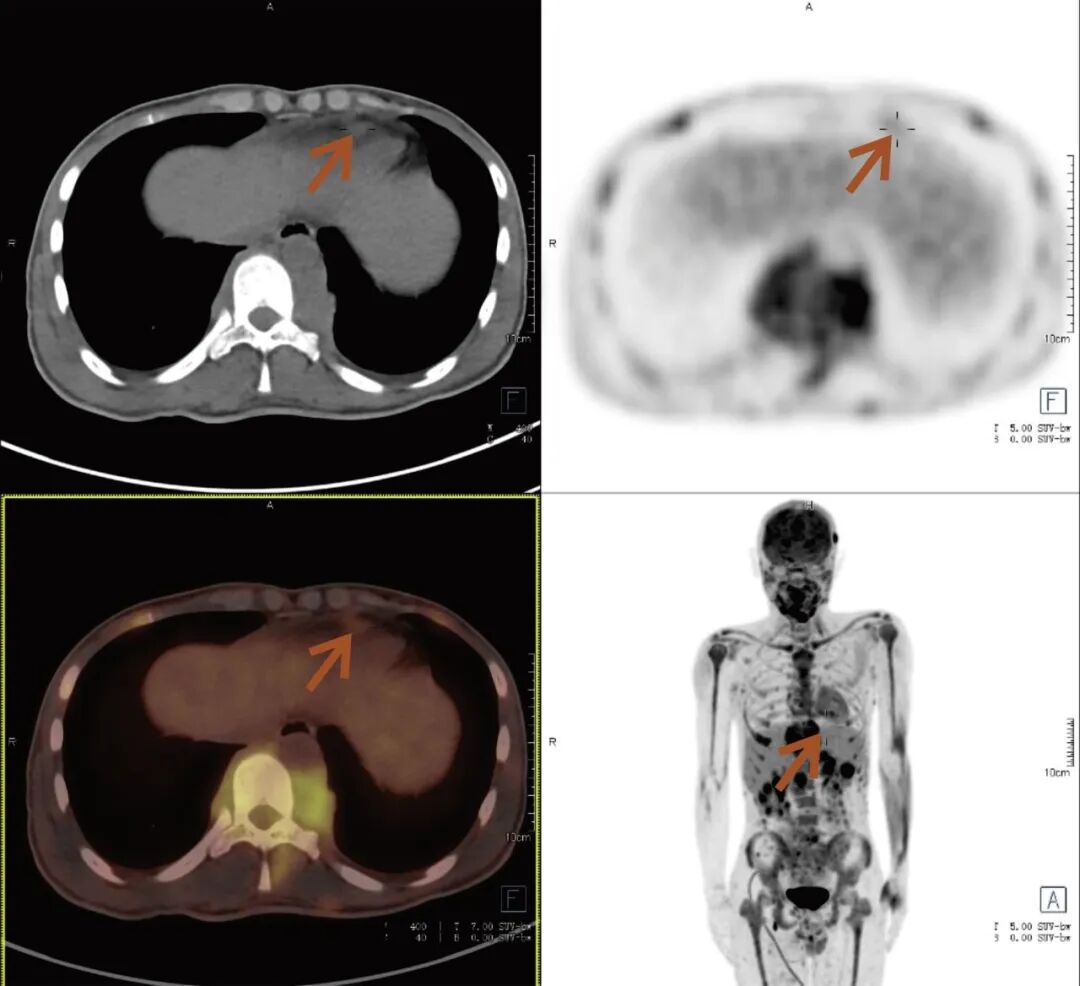

张先生(化名),因持续3个多月的腹痛、腰痛在外院就诊。初始CT检查发现其胸11椎体骨质破坏伴周围软组织肿胀,考虑为“脊柱结核”等感染性病变,并接受了中药治疗。然而,两个月后,张先生又出现了新的症状——牙痛。 经病理活检及免疫组化检查,最终确诊为极为罕见的Erdheim-Chester病。为全面评估这一可累及全身多系统疾病的侵犯范围、明确病灶活动性,并为制定精准治疗方案提供依据,张先生进行了全身PET/CT检查。 PET/CT检查图像: PET/CT检查结果: (1)中轴骨及四肢骨广泛FDG代谢活跃伴信号异常;其中胸10、胸11椎体病灶周围软组织增厚,累及邻近椎管内及双侧椎间孔、双侧胸膜,并与主动脉分界不清。 (2)全身皮下及肌层内多发结节及肿块,FDG代谢活跃;全身软组织广泛肿胀。 (3)鼻咽各壁增厚,顶后壁为著,FDG代谢活跃。 (4)甲状腺多发结节,FDG代谢活跃;双肾及胰腺多发结节及肿块,FDG代谢活跃;双侧阴囊内异常信号伴FDG代谢活跃; (5)左侧锁骨上窝、纵隔内(2L区、3A区)、降主动脉旁、左侧横膈前组、右侧腋窝、左肾周间隙、肠系膜区、双侧髂血管旁多发淋巴结,FDG代谢活跃; (6)心包局部呈结节状稍增厚,FDG代谢轻度活跃; 综上,结合临床,均考虑Erdheim-Chester病所致。 此次PET/CT不仅证实了已知的脊柱病变,更一次性揭示了临床尚未怀疑的、广泛存在于内脏、淋巴结及软组织的隐匿病灶,为疾病分期与治疗提供了决定性依据。